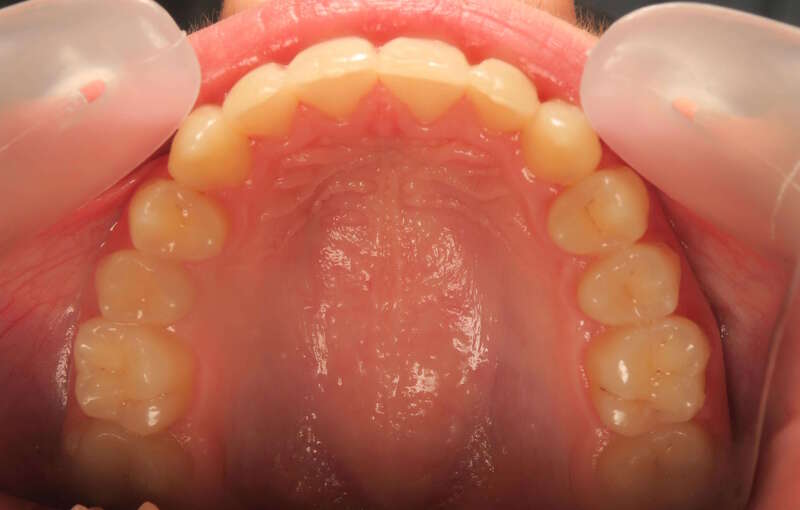

Cas n°10 traité par multi-attaches - adolescent

Ce cas d’adolescent démontre l'efficacité du traitement par brackets autoligaturants pour résoudre un encombrement majeur sans extraction. Initialement, le patient présentait des dents sévèrement chevauchées et exclues de l'arcade par manque de place.

Grâce à la technologie autoligaturante, le traitement a privilégié le développement biologique des arcades. Les forces légères et constantes ont permis d'élargir les arcades de manière physiologique, créant l'espace nécessaire pour aligner chaque dent tout en respectant l'équilibre du profil.

Résultats clés :

• Intégrité dentaire : Conservation de toutes les dents naturelles.

• Harmonie esthétique : Sourire large et aligné qui transforme l'expression faciale.

• Santé parodontale : Alignement facilitant l'hygiène et protégeant les tissus de soutien.

Ce traitement illustre parfaitement l'orthodontie moderne : une approche conservatrice qui optimise la fonction et l'esthétique sans compromis chirurgical ou extractif.